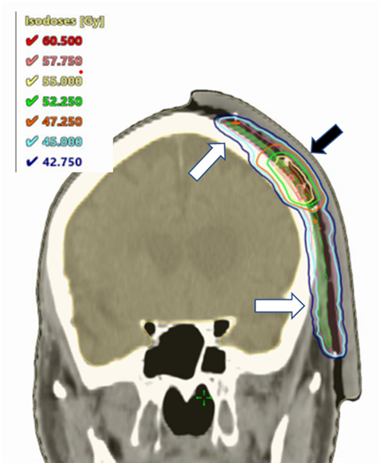

He was treated with lesion-based SXRT to the left nasal ala with a total dose of 50 Gray (Gy) in 25 fractions given at 5 fractions per week. A Xstrahl 300 machine with energy range 50 – 300kVp (Xstrahl Group, Walsall, UK), was used for the delivery of a 100 kVp beam via a three centimetre (cm) circular applicator at 30 cm SSD (source surface distance). For each fraction the nostril was packed with wet gauze and a septal shield was employed to decrease the amount of mucositis. The left frontal scalp was treated with a 0.8 cm gel bolus field-based VMAT technique,6 using a TrueBeamTM Linear accelerator (Varian Medical Systems, Inc., CA, USA) to a planning target volume (PTV)7 of 74.8 cubic centimetres (cm3) to 45Gy (PTV45) with a SIB PTV to 55 Gy of 4.1 cm3 (PTV55-SIB) to the BCC (Figure 4). He was reviewed by the RO on a weekly basis during RT. The RT was completed in the planned time without any break.

Figure 4 Coronal dosimetry of VMAT volume for left temple, planned in Eclipse V15.6 planning system (Varian Medical Systems, Inc., CA, USA). White arrows show PTV45 doses. Black arrow shows PTV55-SIB doses.